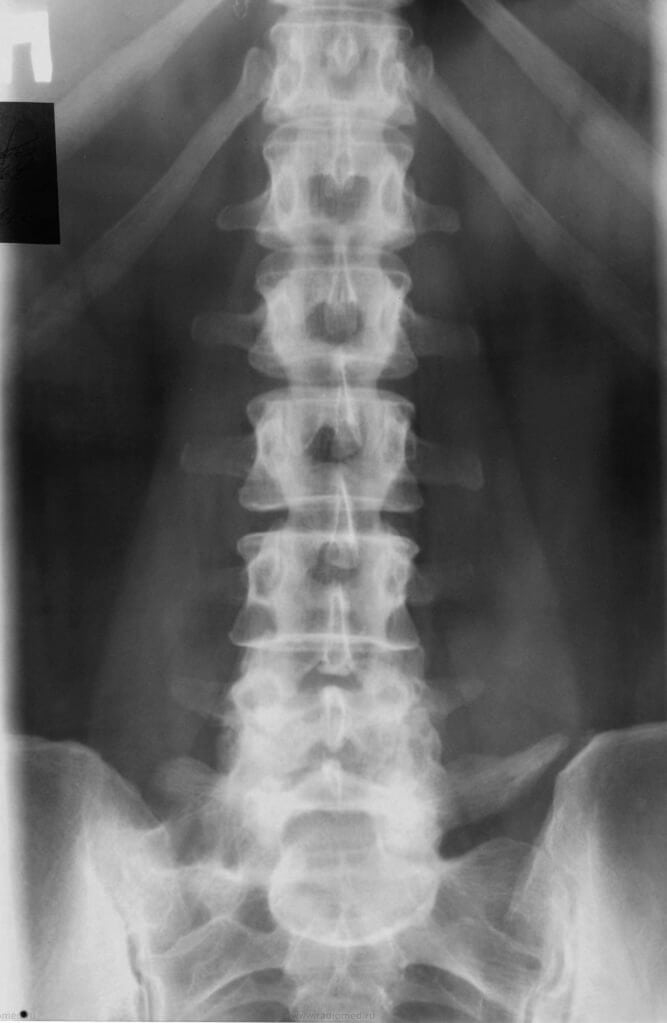

Каждой степени остеохондроза соответствует своя рентгенографическая стадия. Это помогает диагностировать патологию, но часто становится причиной путаницы у больных. Степень характеризует особенности симптоматики, а стадия — структурно-морфологические изменения в позвоночнике. Поясничный остеохондроз соответствует как 1 (доклинической) рентгенографической стадии, так и второй. Поэтому при изучении полученных снимков невропатолог может не обнаружить деструкции межпозвонковых дисков. Но чаще выявляется уплотнение хрящевых тканей, типичное для 2 стадии. Стабильность позвоночника сохранена, но уже хорошо заметно увеличение крючковидных отростков тел позвонков. Межпозвонковый диск смещен минимально, а вот нарушение структуры фиброзной капсулы произошло.